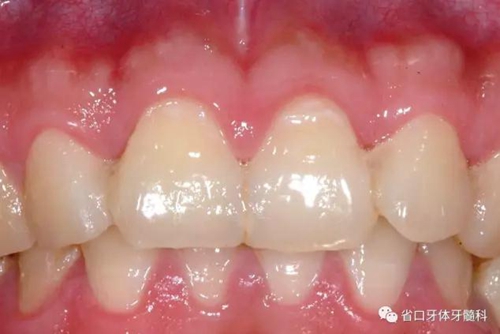

圖8:隨訪口內(nèi)照

檢查:口腔衛(wèi)生良好,牙齦無(wú)紅腫,12-22固位良好,無(wú)松動(dòng),叩診無(wú)明顯不適,電活力測(cè)試21活力值同正常對(duì)照牙,活力值為5;